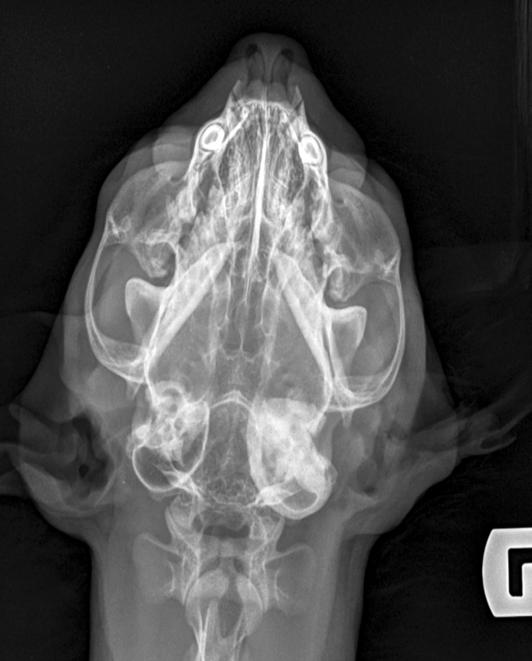

1. Radiografías de la cabeza de un gato maine coon de un año de edad. (A) Proyección lateral. (B) Proyección dorsoventral. (C) Rostro 10º ventrodorsocaudal oblicua.

Se presentó en consulta un gato macho castrado de raza maine coon, de un año de edad y 5,8 kg de peso, remitido con historia de otitis externa desde hacía un mes.

En la exploración otológica se visualizó una masa en el conducto auditivo externo izquierdo, apreciable desde la abertura del pabellón auricular. La masa era sólida, poco móvil y obstruía totalmente el canal auditivo. El resto del examen físico y pruebas de enfermedades víricas fueron normales. En el análisis sanguíneo se evidenció neutrofilia con desviación a la izquierda y trombocitosis.